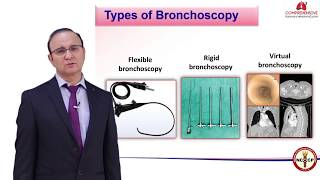

Bronchoscopy Procedure #education #shorts Interventional Pulmonology Part - I - Overview of bronchoscopy I - Dr Rajesh Chawla - CPMC

Interventional Pulmonology Part - I - Overview of bronchoscopy I - Dr Rajesh Chawla - CPMC Training to Competence in Interventional Pulmonology | BRONCHUS 2023 | Yashoda Hospitals Hyderabad

Training to Competence in Interventional Pulmonology | BRONCHUS 2023 | Yashoda Hospitals Hyderabad Interventional Pulmonology Part - I - Overview of bronchoscopy II - Dr Rajesh Chawla - CPMC

Interventional Pulmonology Part - I - Overview of bronchoscopy II - Dr Rajesh Chawla - CPMC Bronchoscopy Technique - Dr. Nimisha A.K. Consultant Interventional Pulmonologist - Moulana Hospital

Bronchoscopy Procedure #education #shorts Interventional Pulmonology Part - I - Overview of bronchoscopy I - Dr Rajesh Chawla - CPMC

Interventional Pulmonology Part - I - Overview of bronchoscopy I - Dr Rajesh Chawla - CPMC Training to Competence in Interventional Pulmonology | BRONCHUS 2023 | Yashoda Hospitals Hyderabad

Training to Competence in Interventional Pulmonology | BRONCHUS 2023 | Yashoda Hospitals Hyderabad Interventional Pulmonology Part - I - Overview of bronchoscopy II - Dr Rajesh Chawla - CPMC

Interventional Pulmonology Part - I - Overview of bronchoscopy II - Dr Rajesh Chawla - CPMC Bronchoscopy Technique - Dr. Nimisha A.K. Consultant Interventional Pulmonologist - Moulana Hospital